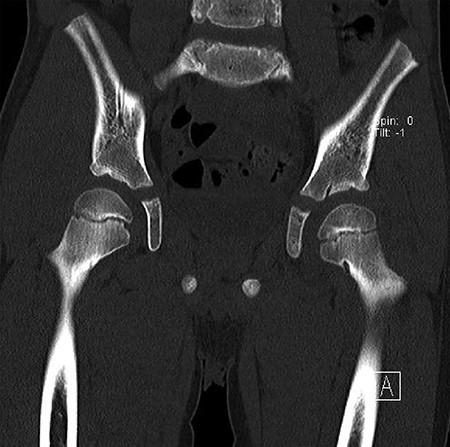

CT hips reported a well-defined lesion seen bilaterally in the neck of femur anterior infero-medial aspect, more prominent on the left side measuring 7 x 3 mm on left side both in coronal (Fig. 3) and axial (Fig. 4) views. On the right side, other lesion measuring 2 x 1 mm (Fig. 5) seen in coronal view. These two lesions are well defined with a sclerotic border with a small cortical defect. The lesion shows fat density. The symmetrical appearance of the lesion combined with the fat density and location suggest the diagnosis of synovial herniation pit. MRI Pelvis revealed minimal left hip joint effusion with loculated fluid seen along the trochanteric bursa with the largest measuring 0.9 x 1.5 cm (Fig. 6, 7).

Sowed coronal cut of CT hips demonstrating the synovial pit on left and right side.